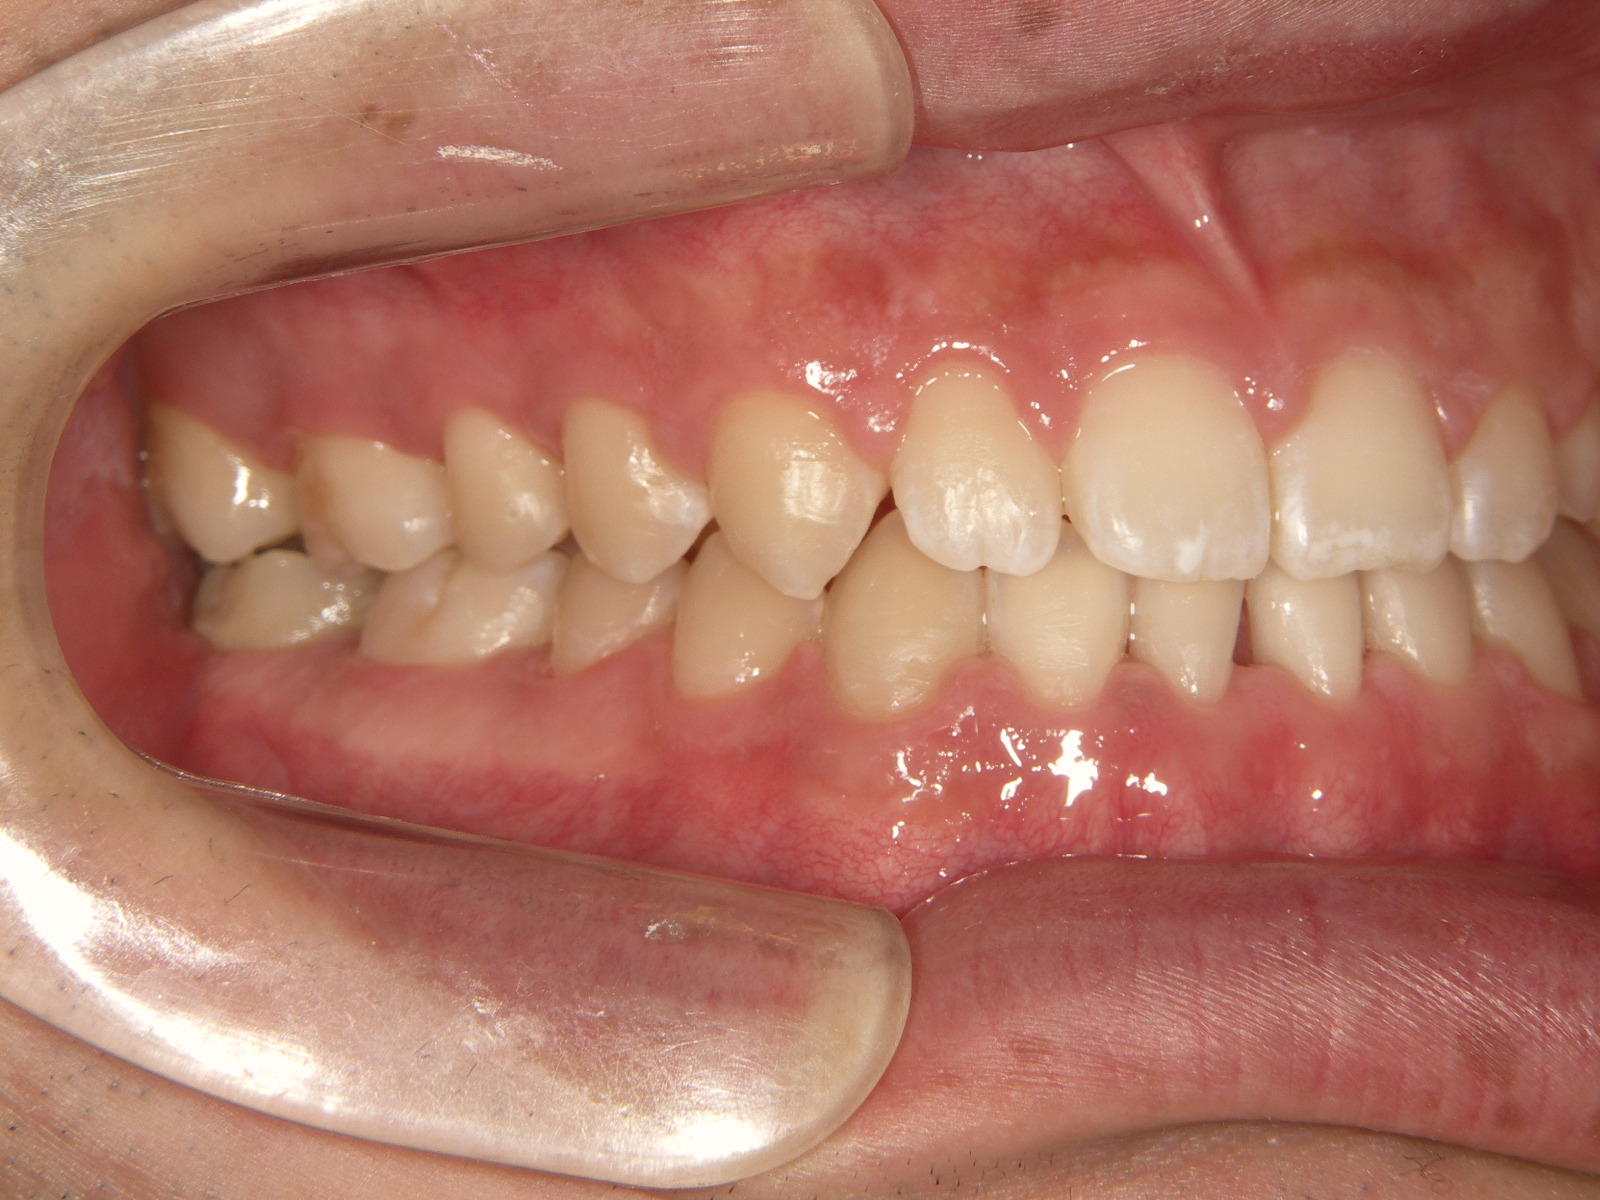

① 治療前

受け口(反対咬合)の状態です。下顎が前方に突出しています。